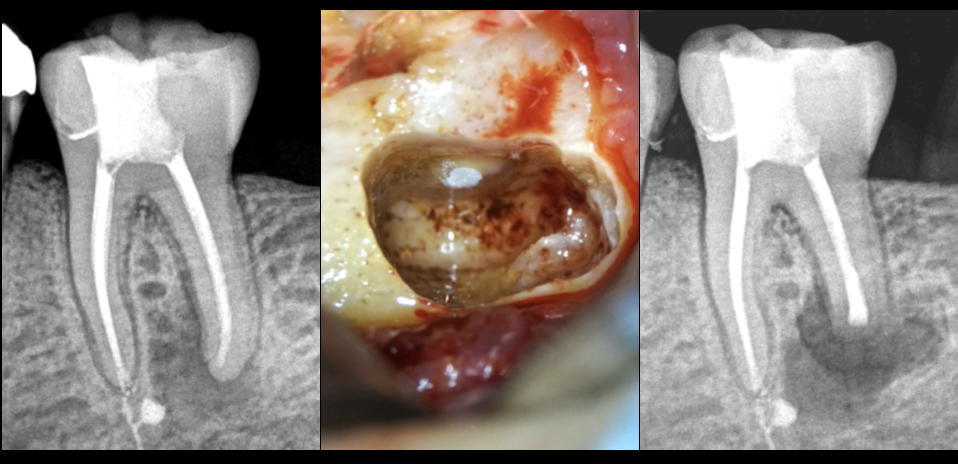

🔍 Restauration précédemment réalisée avec coiffage pulpaire par un praticien

🗓️ Le jour de notre consultation : pulpe nécrosée, parodontite apicale symptomatique